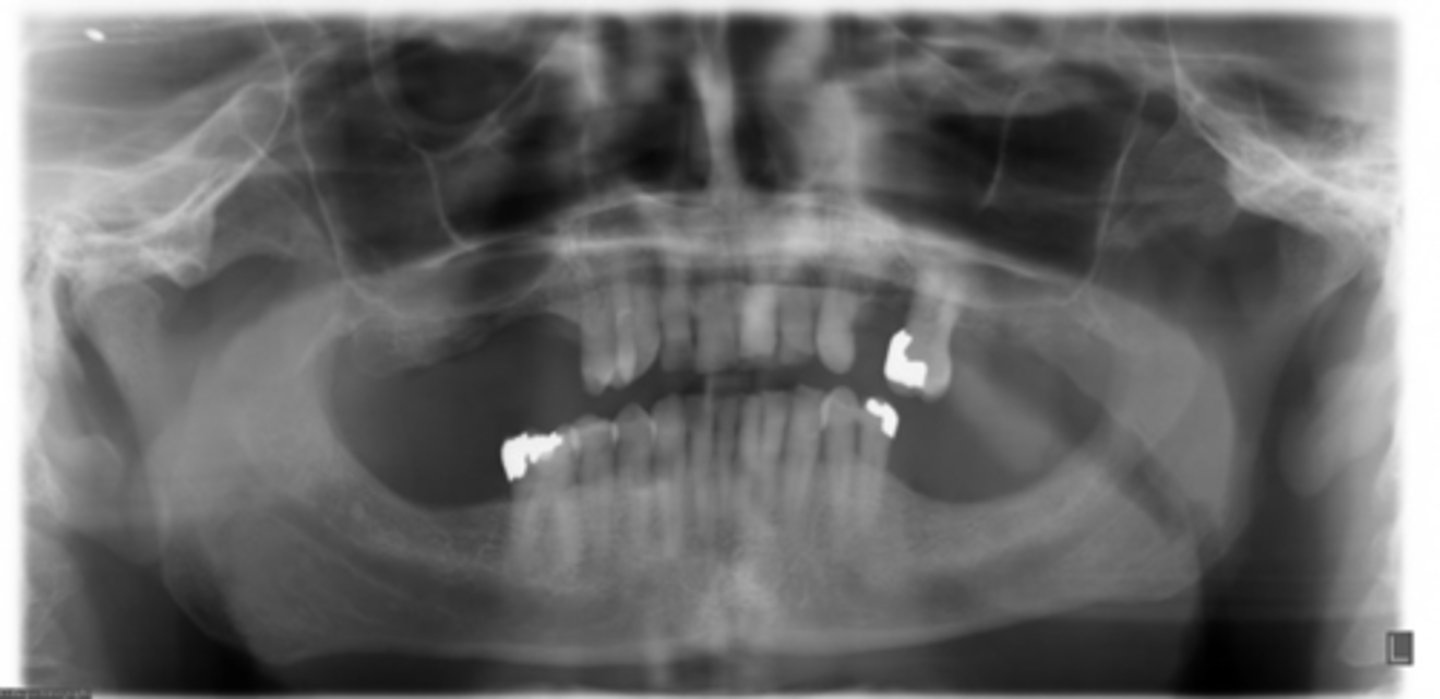

ID the positional error from the radiograph:

too far back (short/wider incisors)

(and right rotation)